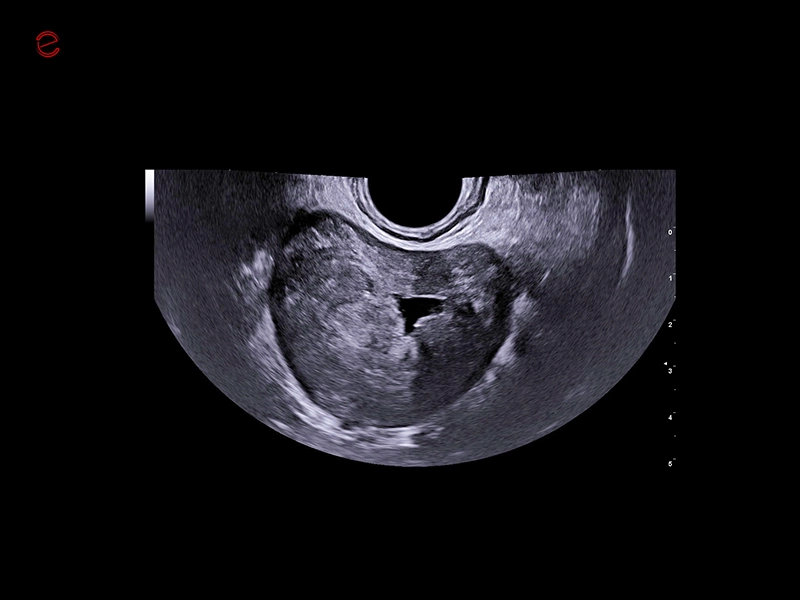

Q7 - Endo

Q7 - Endo